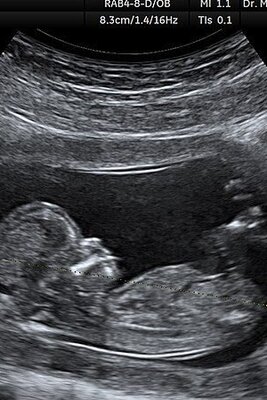

خمیازه کشیدن بامزه جنین در شکم مادرش +فیلم سونوگرافی😍/دل آدم میره براش

پربازدید شدن حرکات جالب جنین 8 ماهه در شکم مادر با سونوگرافی 4 بعدی/ دل مامانش براش ضعف رفت😍+عکس

گریه و خنده های بامزه ترین نوزاد دنیا تو شکم مامانش هنگام سونوگرافی/ دل یه ملت براش ضعف کرد+ویدیو

واکنش خنده دار و بامزه جنین در شکم مامانش به طعم غذا هنگام سونوگرافی/ آخه لب و لوچشو ببین😍

سونوگرافی عجیب الخلقه ترین جنین دنیا که با پرنده اشتباه گرفته شد/ مامانش تا دنیا بیاد چندتا سکته ناقص رد کرده+عکس

عکس | گریه احساسی بچه داخل رحم به خاطر ناراحتی مادرش در سونوگرافی /دل آدم ضعف میره براش

خنده های شیرین تر از قندِ یک جنین در سونوگرافی به خاطر ذوق مادرش/ دلم آدم برای عشق مادر و فرزندیشون ضعف میره+ویدیو

(ویدئو) عادت خنده دار و بامزه یک نوزاد در شکم مامانش هنگام سونوگرافی قند تو دل یه ملت آب کرد😍

(فیلم) واکنش خندهدار و بامزه جنین به شعر خواندن پدر و مادرش در شکم هنگام سونوگرافی / داره دست میزنه برای مامان و باباش 😍

(فیلم) واقعی ترین و طبیعی ترین تصویر از یک جنین 20 هفته ای داخل شکم مادر/قدرت خدارو ببین😍

قیافه و شکل جنین در سونوگرافی های بارداری